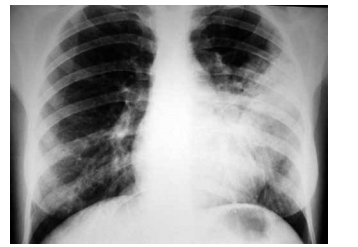

Leia o enunciado a seguir e responda a questão.

Paciente do sexo feminino, 66 anos, com antecedentes de tabagismo, hipertensão arterial sistêmica e diabetes mellitus tipo 2, procura atendimento médico com queixa de desconforto retroesternal tipo queimação e opressão que se iniciou há 1 mês, desencadeado aos grandes esforços. Há 1 semana passou a apresentar os mesmos sintomas em repouso, associados à dispneia, com duração de até 8 minutos e melhora espontânea. A paciente faz uso de valsartana 80 mg, glimepirida 4 mg e metformina 1000 mg. O exame físico é normal, PA = 150x85 mmHg e frequência cardíaca de 96 bpm. O eletrocardiograma está ilustrado a seguir.